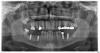

SergioS Опубликовано 13 февраля, 2013 Автор Поделиться Опубликовано 13 февраля, 2013 (изменено) +1а сколько Ваши фрезы уже "работают"?Фрезы новыеСнимок вот Изменено 13 февраля, 2013 пользователем SergioS Ссылка на комментарий

kriokov Опубликовано 13 февраля, 2013 Поделиться Опубликовано 13 февраля, 2013 через 6 недель снимок сделать повторно, если с костью все ОК будет, вкрутить изменив немного направление и может заглубить чуть, до канала там расстояние не маленькое.На снимке деструкция выражена дистальнее винта, грануляции могли просто сожрать дистальную костную стенку.Как сейчас рана в области удалившегося винта заживает? Ссылка на комментарий

johniola Опубликовано 13 февраля, 2013 Поделиться Опубликовано 13 февраля, 2013 Фрезы новыеСнимок вотФрезы новыеСнимок вот мне больше не нравится 35.там агрессивная резьба и наверное была компрессия( посмотрите на снимок).а 37 скорее всего недокрутили имхо Ссылка на комментарий

kriokov Опубликовано 13 февраля, 2013 Поделиться Опубликовано 13 февраля, 2013 мне больше не нравится 35.там агрессивная резьба и наверное была компрессия( посмотрите на снимок).а 37 скорее всего недокрутили имхонормально все с 35, на орто часто так фонит Ссылка на комментарий

Bier Опубликовано 13 февраля, 2013 Поделиться Опубликовано 13 февраля, 2013 бывает такое, что имплантат грануляциями выдавливается.35 кстати - не похоже, что фонит. а толщины кости то хватало там? Ссылка на комментарий

777white Опубликовано 13 февраля, 2013 Поделиться Опубликовано 13 февраля, 2013 Согласен с Биром. По снимку пора и 34 убирать... Похоже все таки из за грануляции не убранных до конца.Имплантам ппц ( Ссылка на комментарий